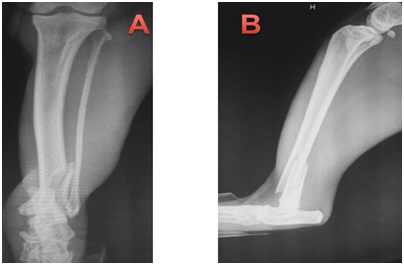

This paper reports the use of a combination of cerclage wire and a neutralization plate in two cats, resulting in primary bone healing. Two non-pedigree male cats (cat 1 and 2), cat 1 weighing 4.1kg and cat 2 weighing 3.9kg, were presented at the Veterinary Hospital of the Federal Univer- sity of Paraná following automobile trauma. General physical examination was unremarkable apart form orthopedic abnormalities. On orthopedic examination, instability, pain and crepitatus were found in the distal region of left tibia and fibula, indicative of fracture. Ventrodorsal and right lateral thoracic radiographs (to rule out pulmonary contusion) were made as well as craniocaudal and lateral views of the tibial and left fibula processes. One cat was presented with a closed tibial fracture. Pre-operative radiographs showed long oblique fractures of the distal third of the tibial diaphysis. The radiographs of the affected limbs of animals 1 and 2, are (Figure 1) (Figure 2), respectively.

Figure 1 Cat 1, with diagnosis of oblique fracture in the distal region of the left tibia and transverse fracture in the left distal fibula.

1. Craniocaudal projection showing oblique fracture in the distal tibia.

2. Mid-lateral projection with oblique fracture visible in the distal tibia.

Figure 2 Cat 2, with diagnosis of oblique fracture in the distal region of the left tibia and transverse fracture in the left distal fibula.

1. Lateral-medial projection with oblique fracture in the left distal tibia.

2. Craniocaudal projection showing oblique fracture in the distal tibia.